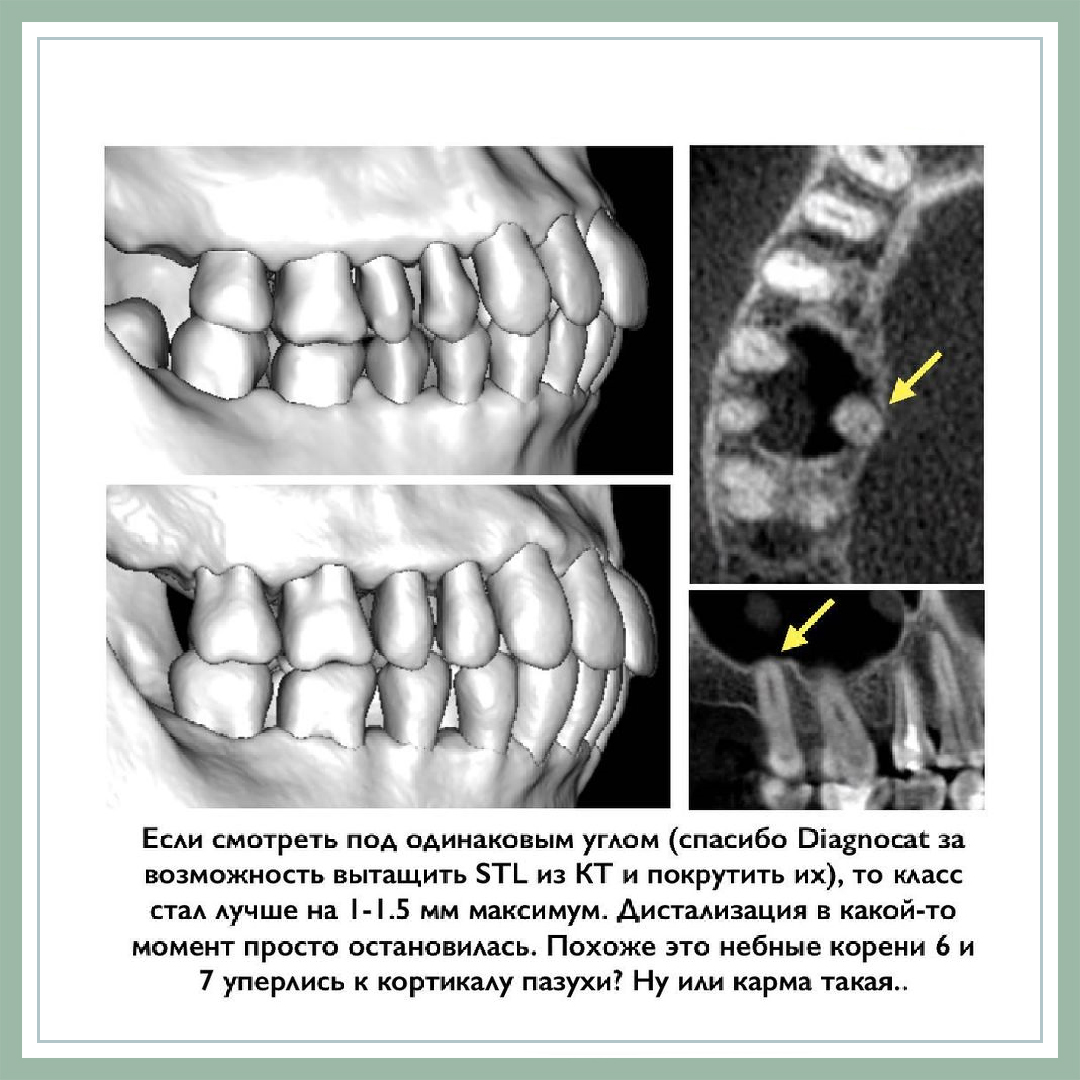

- Расширение у взрослых пытается рецидивировать, посмотрим еще, но тенденция есть и у данного пациента.